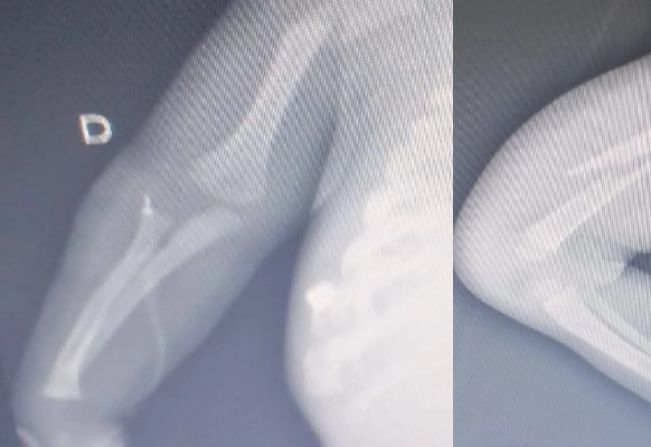

Os exames médicos revelaram fraturas nos braços, fêmur e costela, além de perfuração pulmonar e hematomas pelo corpo. Suspeitando de maus-tratos, a equipe médica acionou o Conselho Tutelar, que solicitou apoio à Guarda Civil Municipal (GCM).